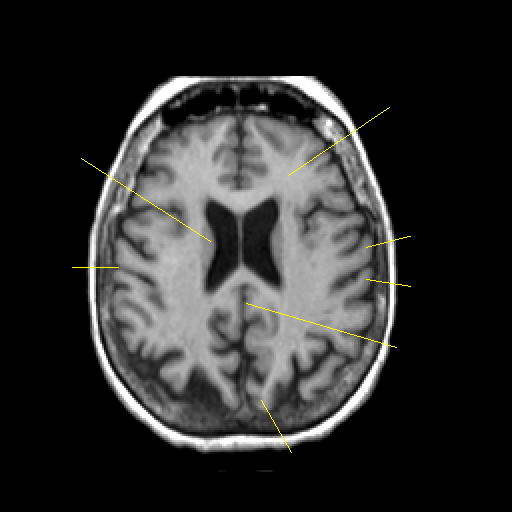

T1-weighted structural MR: Slice 34

Slice 34

Pointers

Labeled